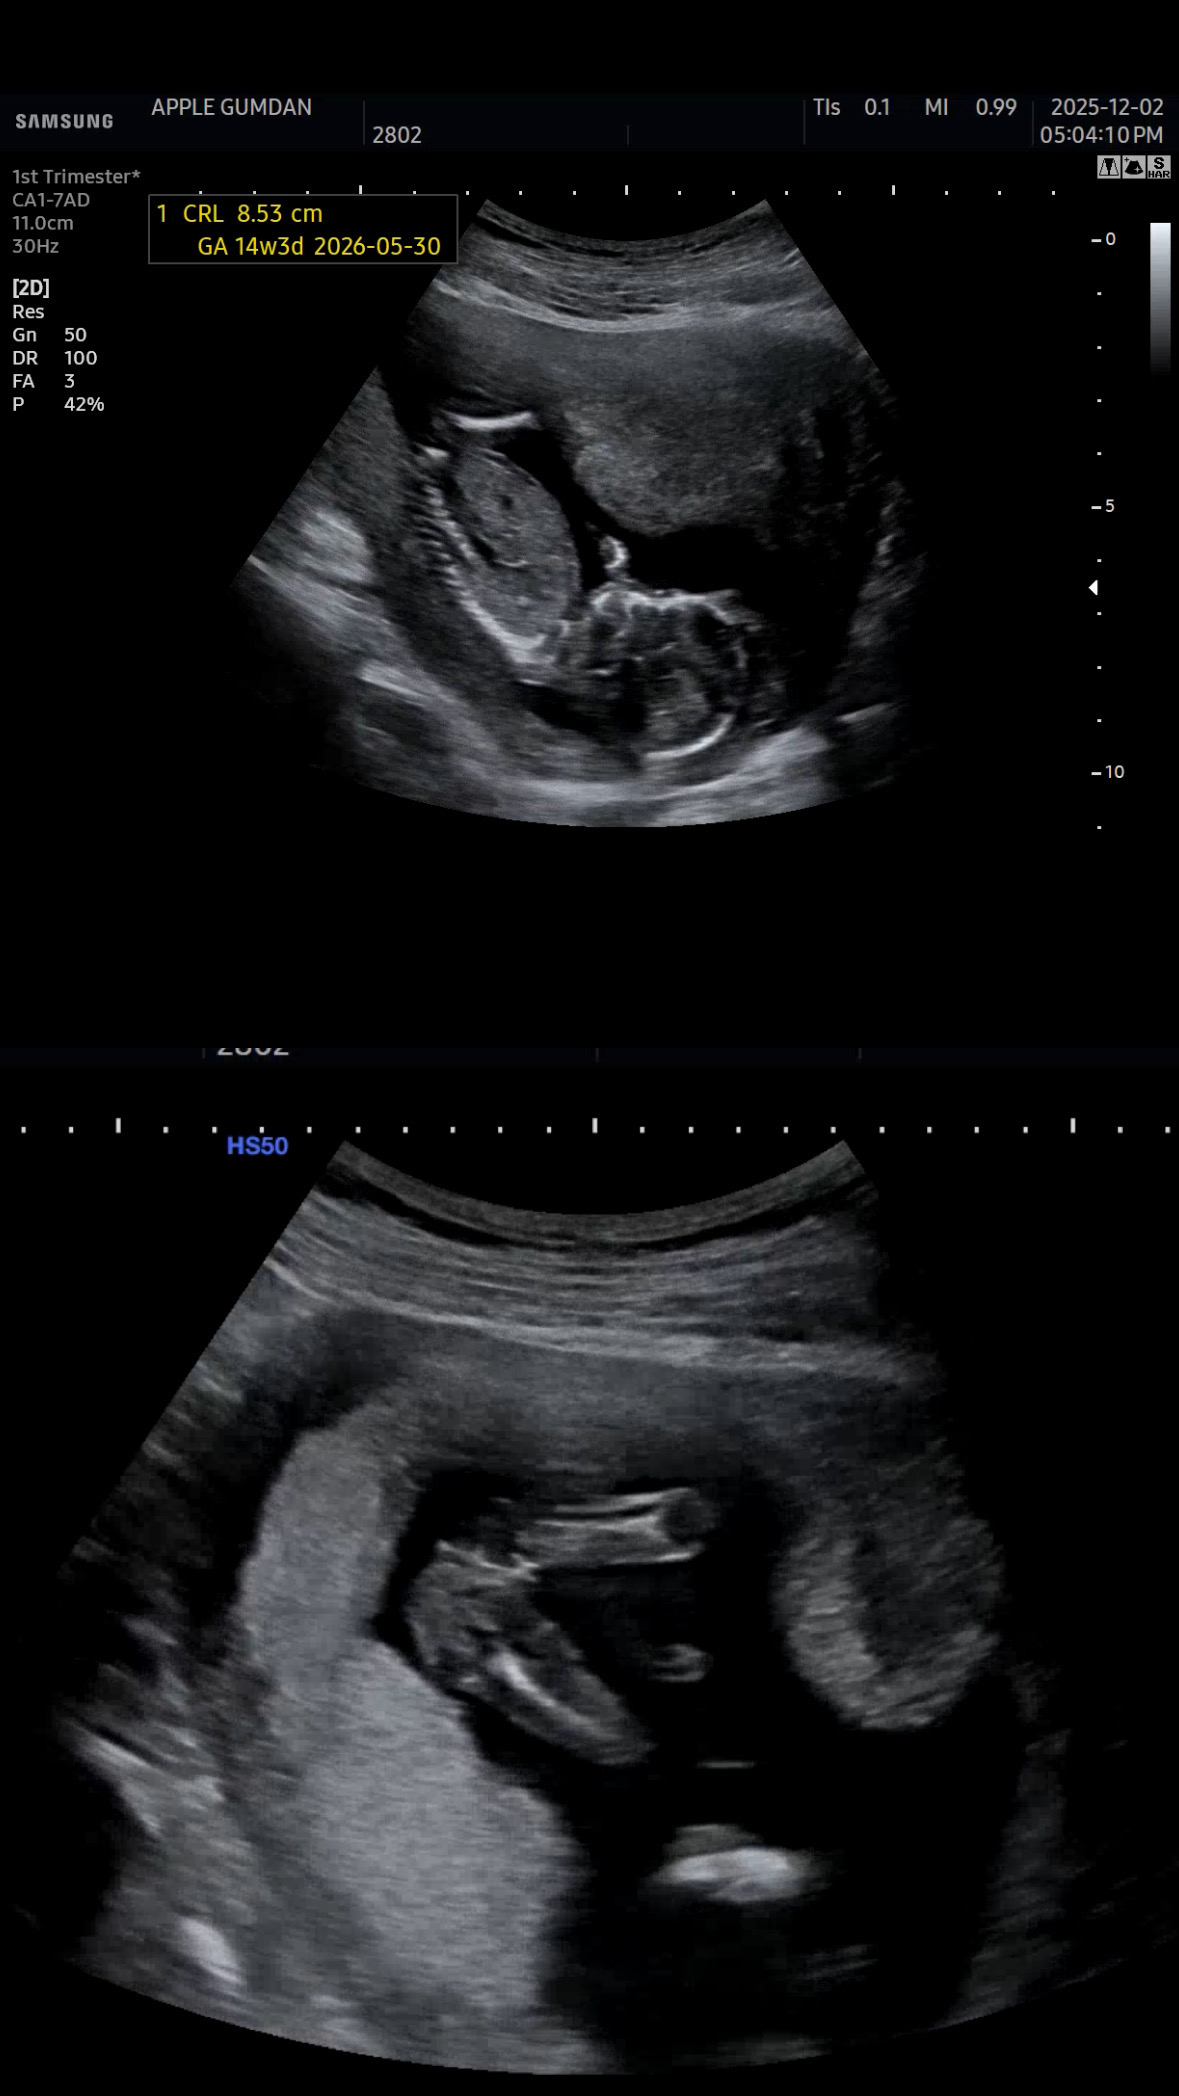

딸일까요 아들일까요👶🏻☃️

삼각점이안보이는게 딸같아 보입니다아

아래 사진은 딸같은데요!!

밑에사진으론 딸같아요